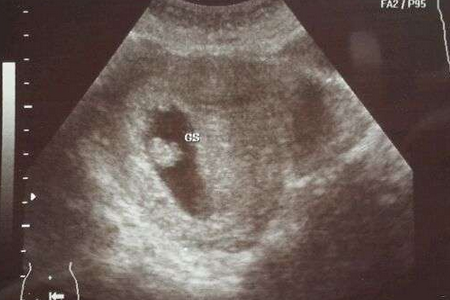

怀孕两个月胎儿发育情况

孕2月胎儿迅速生长,与孕早期心脏和大脑的发育时的速度相当,并在几周中显现出明显的轮廓。到第8周末,胎儿将长到3厘米左右、体重约有4克;胎盘脐带形成;皮肤像纸一样薄,血管清晰可见;用肉眼就能分辨出头、身体和手足;已经会做踢腿、伸腿、抬手、移动双臂的小动作了——不过此时丝毫也查觉不到。